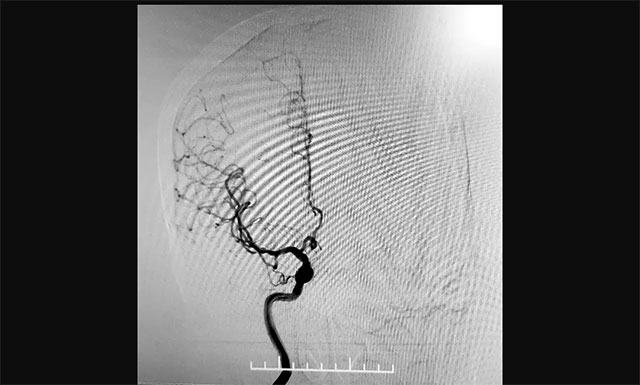

2020年12月22日,75岁的患者吴女士(化名)因“头晕头胀1月余,加重1天”入院。头颅CTA:双侧颈内动脉C4-6段钙化斑形成,伴相应管腔轻度狭窄;双侧大脑前动脉A2段、大脑中动脉远端分支、双侧大脑后动脉P2-3段多发局灶性轻-中狭窄。为做鉴别诊断并了解脑血管情况,有必要进行脑血管造影检查进行评估。

▲ 与传统经股动脉穿刺脑血管造影相比,经桡动脉穿刺造影相对复杂,但手术创伤小、穿刺点血肿发生率较低

考虑到患者年龄较大,不适宜长时间卧床,张琪博士遂决定经桡动脉入路行全脑血管造影术。经过详细的术前准备,2020年12月26日,张琪博士带领介入团队成功为患者进行了手术,术程顺利,耗时约30分钟,术后予桡动脉压迫器压迫术口,术后护理简单,不影响康复治疗,无术后制动,获得病人及家属的一致好评。